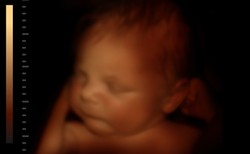

5 Popularnym badaniem prenatalnym jest USG płodu. Podczas niego sprawdza się wymiary poszczególnych narządów płodu, kości nosowych, udowych, a także pracę serca. Pozwala to wykryć zespół Downa, Turnera, Edwardsa, wrodzone wady serca, wodogłowie, rozszczep wargi, kręgosłupa, a nawet karłowatość. Takie USG wykonuje się w ok. 13. oraz 24. tygodniu ciąży